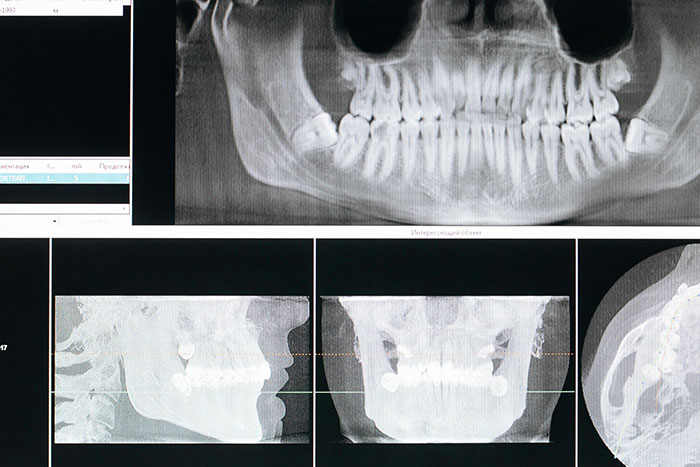

#8

The health of your teeth, or lack thereof, can cause heart disease. The bacteria that infect the gums and cause gingivitis and periodontitis also travel to blood vessels elsewhere in the body, where they cause blood vessel inflammation and damage.

If you are diabetic, and don't know it--or do, but have problems controlling your sugars, it can severely harm your teeth. On the flip side? Having bad teeth can severely affect your blood glucose as a diabetic. It can become a s****y cycle.

And yes--mentioned earlier, but if you get an infected tooth, that infection can travel to the brain or blood very fast.

And yet, teeth are still considered "luxury bones," with maintenance, cleaning, and dental care hardly ever being covered by insurance.